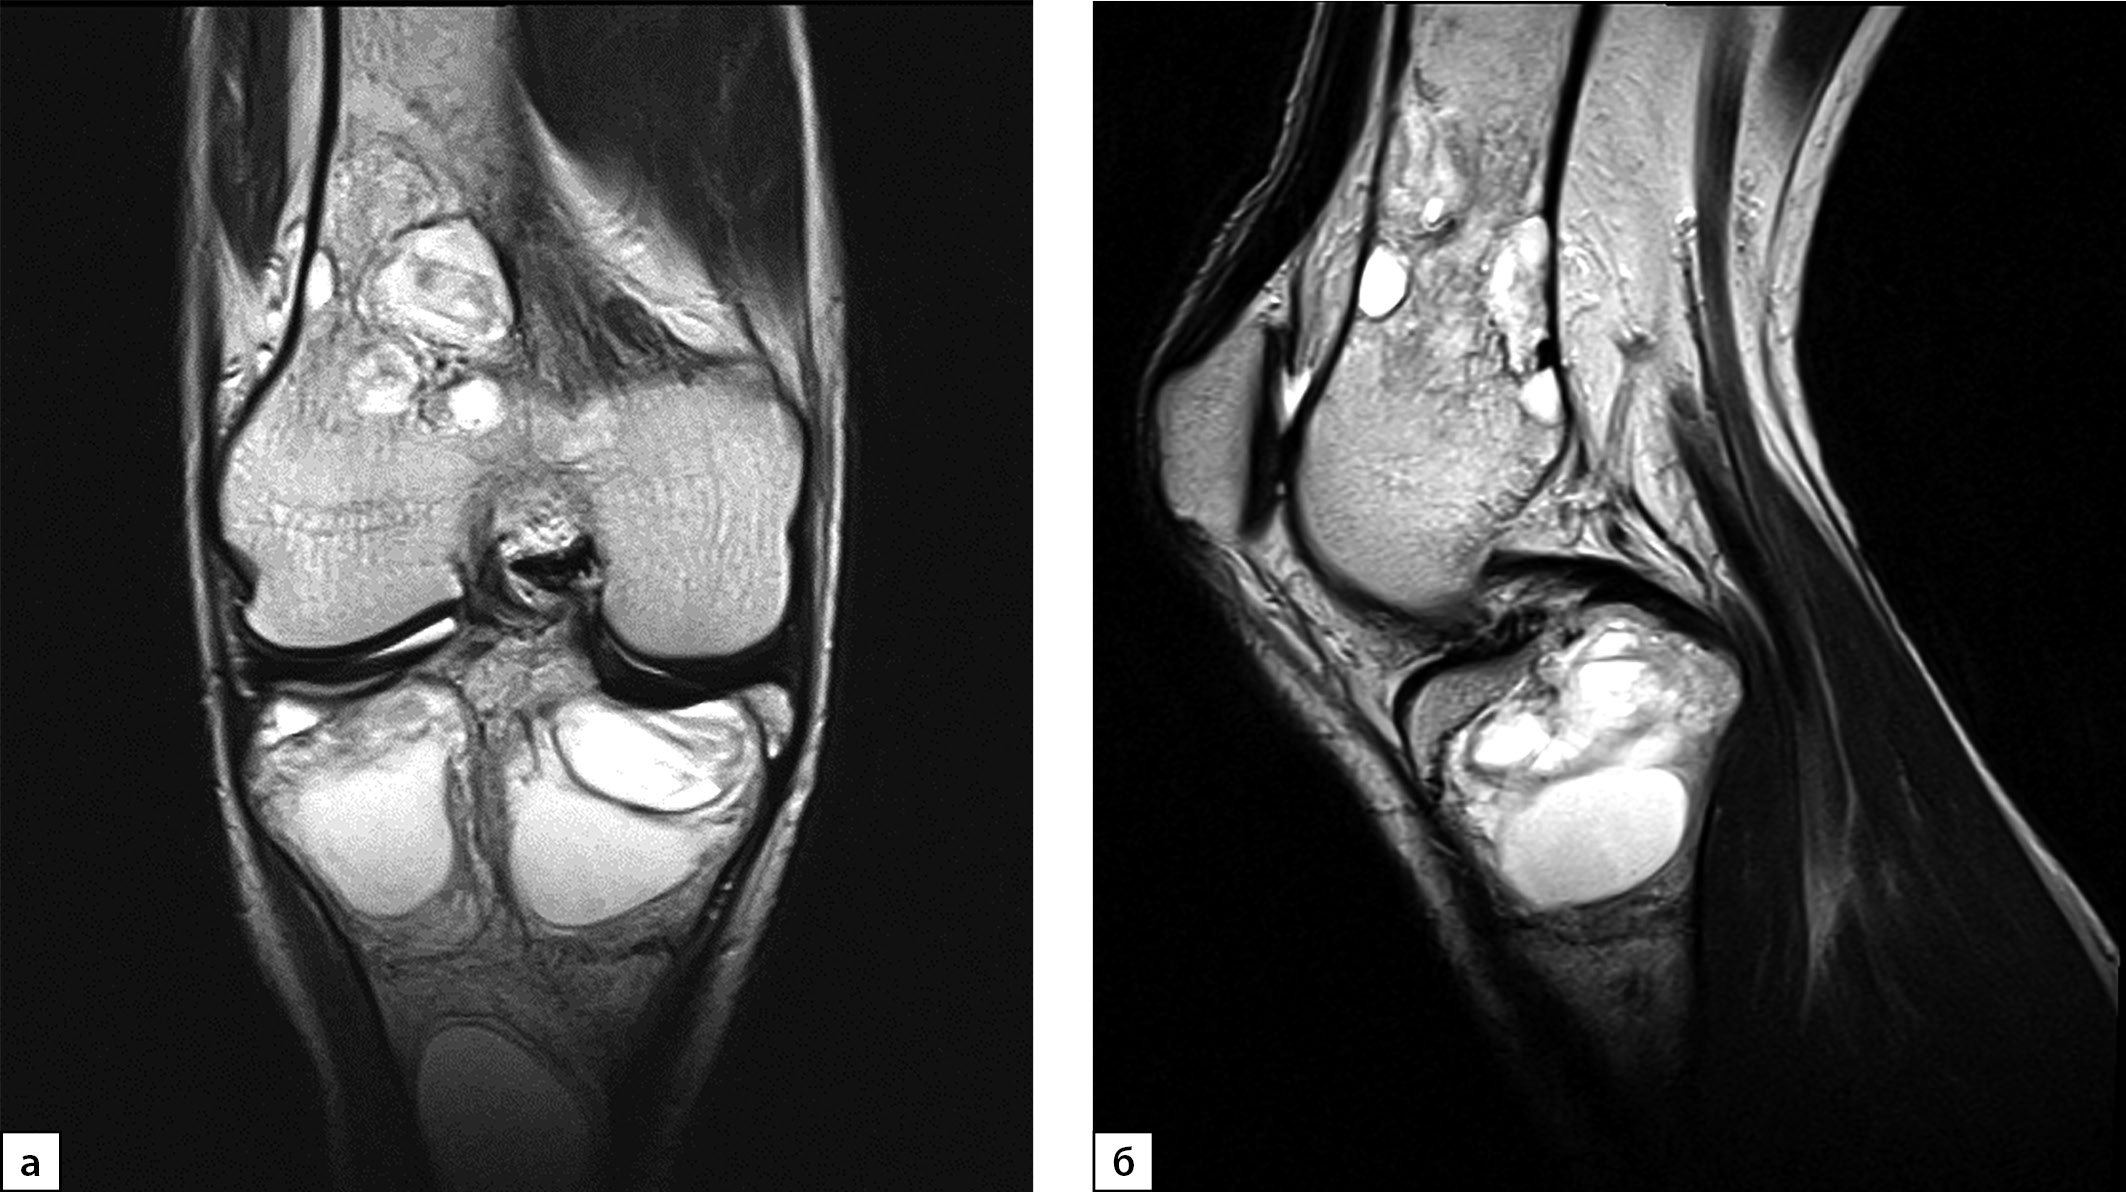

В июле 2020 г. после низкоэнергетической травмы (падения) при рентгенологическом исследовании правого коленного сустава выявлены множественные очаги деструкции костей, образующих коленный сустав. Данные изменения расценены как множественные кисты (рис. 1, а, б). По данным магнитно-резонансной томографии (МРТ) также подтверждены признаки множественных кист в дистальных метаэпифизах бедренных и проксимальных отделах большеберцовых костей с обеих сторон, справа — с разрушением кортикального слоя кости (рис. 2, а, б).

Рисунок 2. Магнитно-резонансная томография правого коленного сустава в режиме Т2, 2020 г. (в корональной (а) и сагиттальной проекциях (б)): МР-картина множественных костных кист в бедренной и большеберцовой костях. Отмечается истончение кортикального слоя кости, местами вздутие.